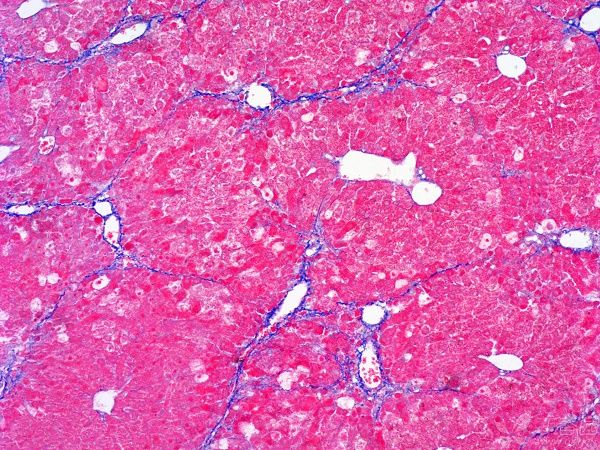

MASSON染色利用不同染料分子與組織結(jié)構(gòu)的相互作用,實現(xiàn)對膠原纖維和肌纖維的精準(zhǔn)區(qū)分。在染色過程中,肌纖維呈現(xiàn)為紅色,而膠原纖維則呈現(xiàn)為綠色或藍(lán)色。這種色彩對比使得纖維組織在顯微鏡下變得清晰可見,醫(yī)生能夠清晰地觀察到纖維化的程度和范圍。

圖1. Masson組織染色結(jié)果示例(最右列),可看到不同處理條件下膠原纖維(藍(lán)色)和肌纖維(紅色)的分布不同

①正常組織染色結(jié)果

在正常組織中,MASSON染色通常呈現(xiàn)出均勻的藍(lán)色背景,其中肌肉纖維和血管等結(jié)構(gòu)清晰可見。這種染色結(jié)果表明組織結(jié)構(gòu)正常,無明顯的纖維化病變。